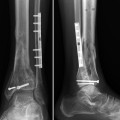

Fig. 1

(a) Anteroposterior radiograph at time of referral to our institution. (b) Lateral radiograph corresponding to Fig. 1a